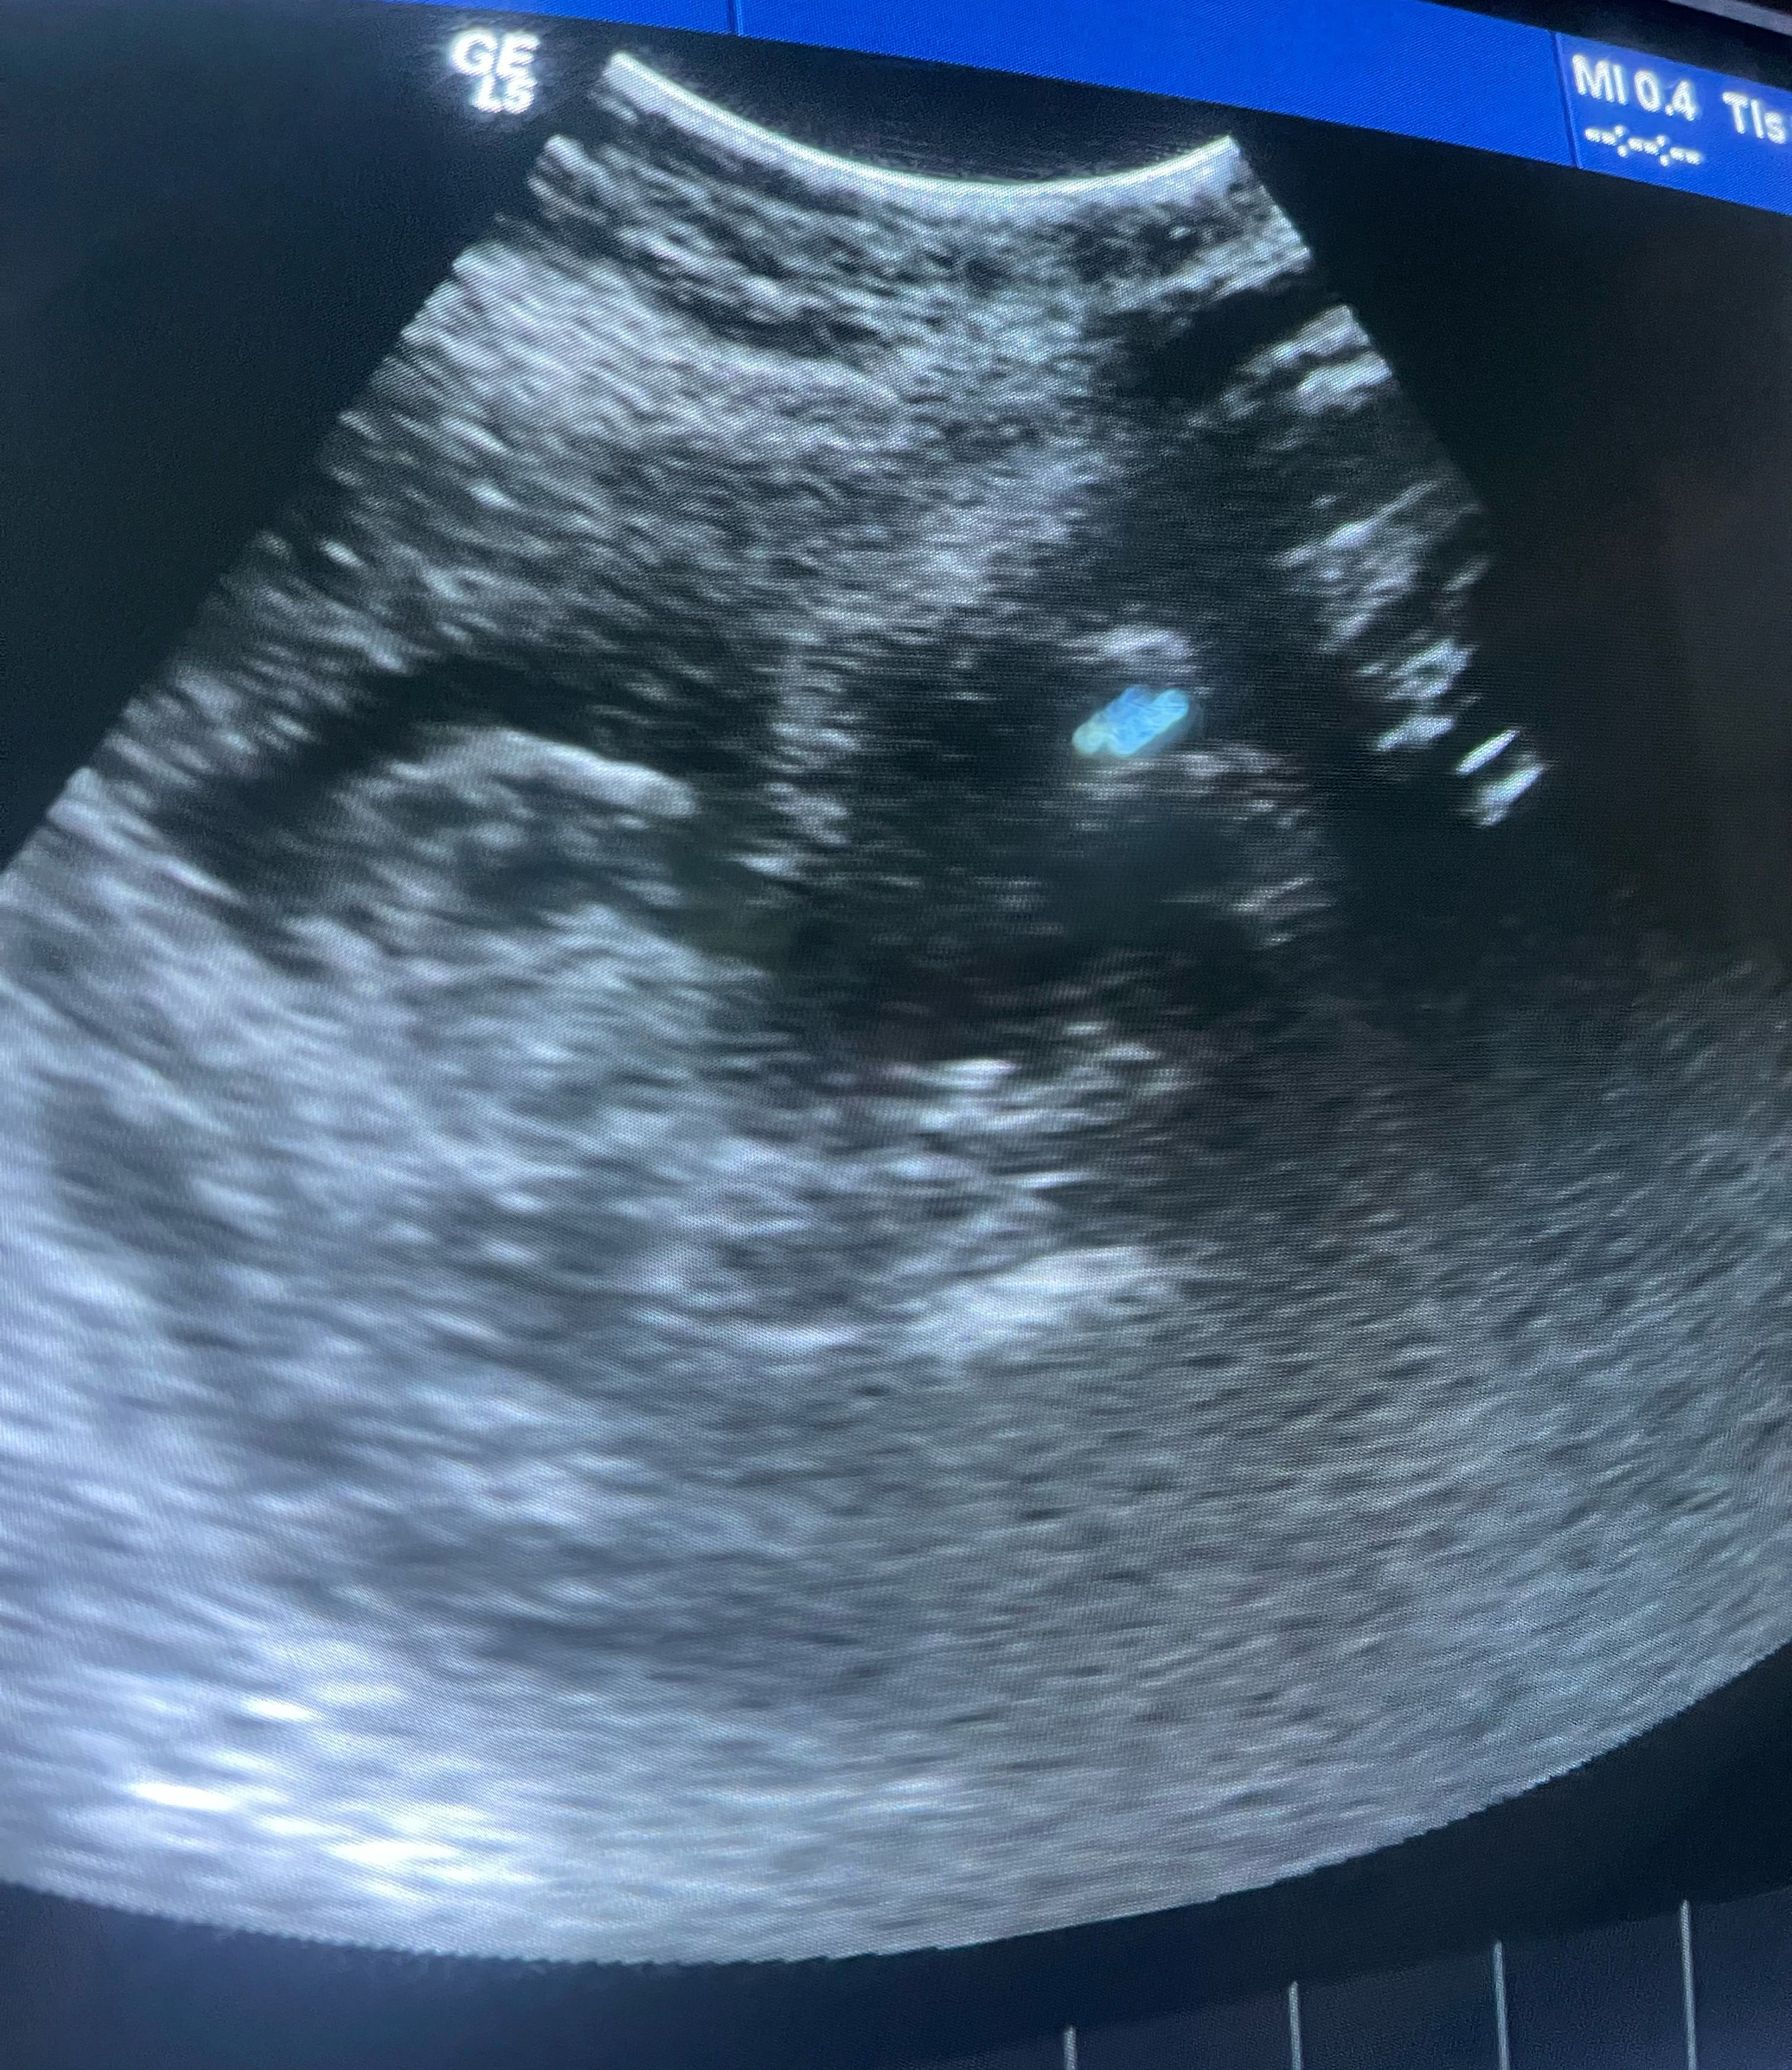

Gender??

Comment what you see in this ultrasound

Ultrasound

Gender